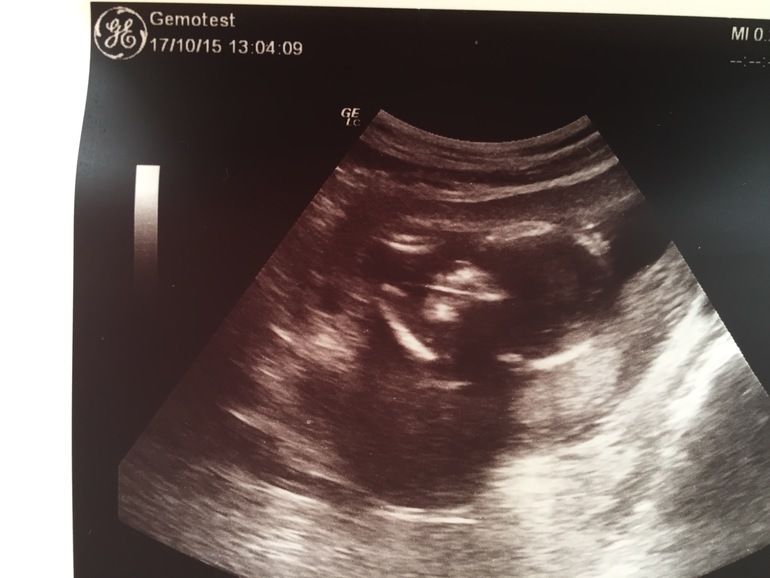

Узи и пол

Пол малышасегодня ходила на узи , и врач увидела что это мальчик ) ну 2 брата тоже хорошо ) есть небольшой тонус . Посмотрим что скажут на 21 неделе )